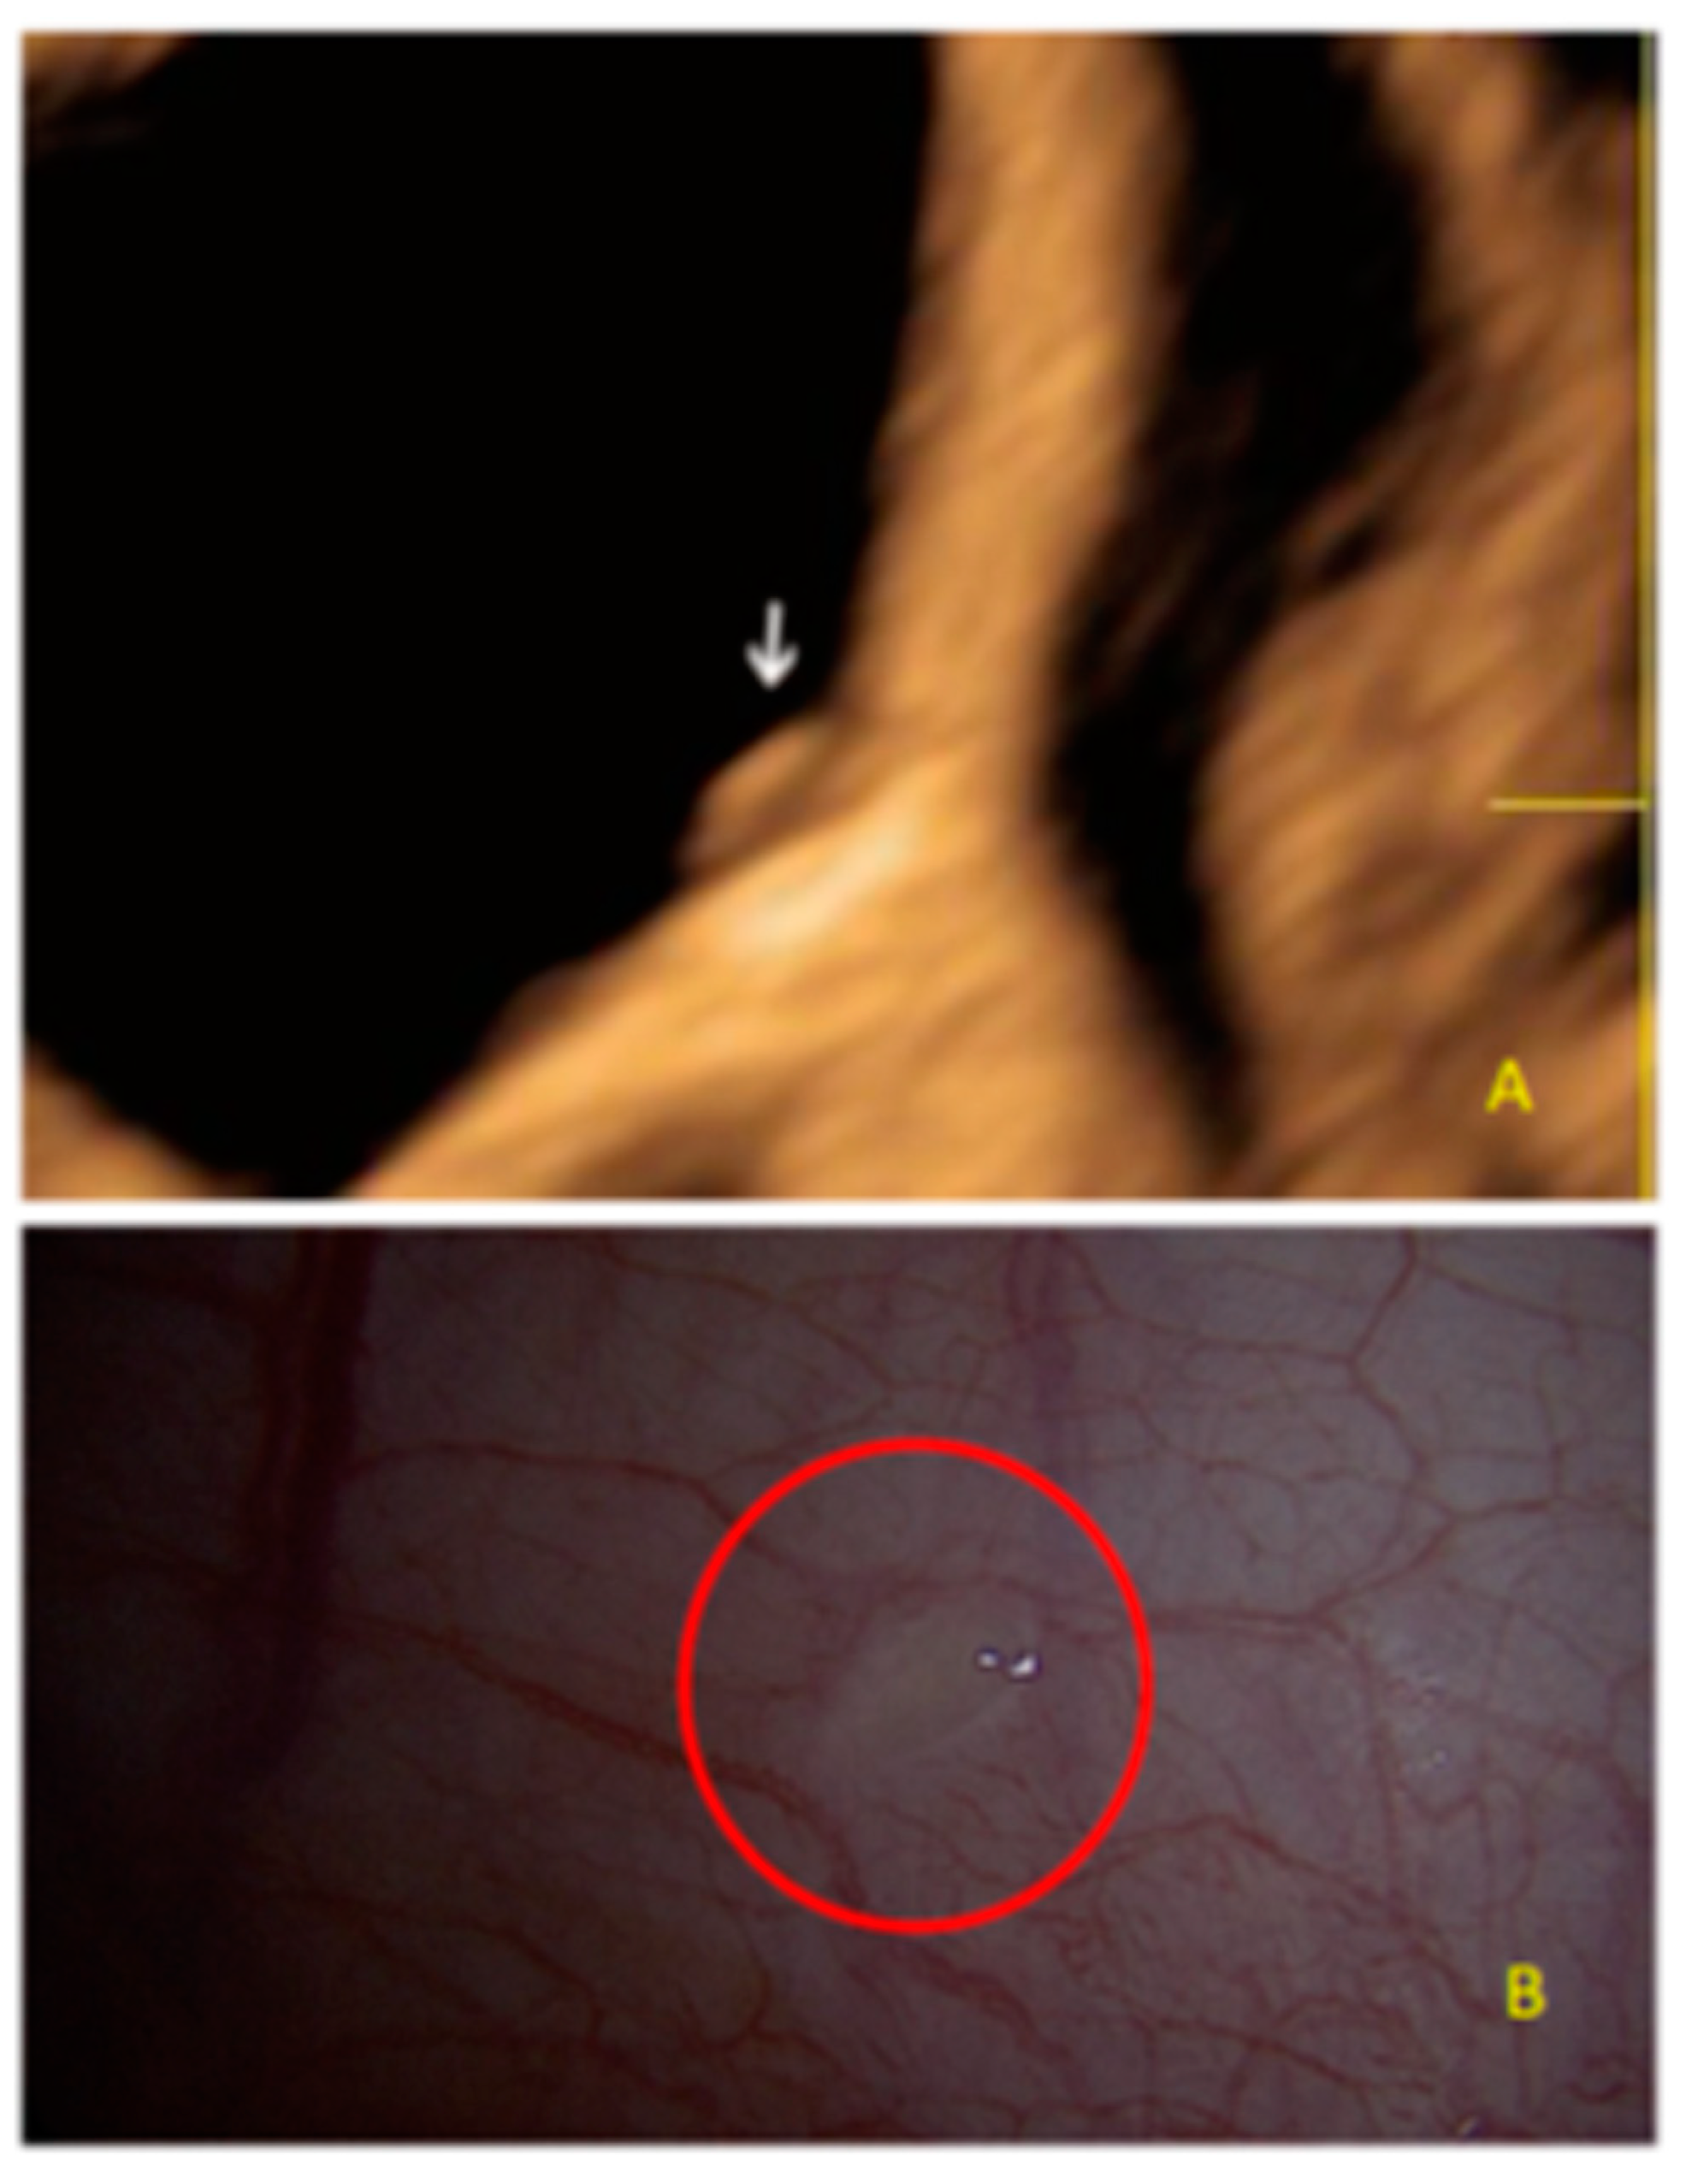

- The lesion may be convex, protruding from the peritoneal surface into the peritoneal cavity (we called this “bulging”), or it may appear as a concave defect in the peritoneum (we called this a “pocket”).

- The presence of hyperechoic foci (we called this a “pearl”).